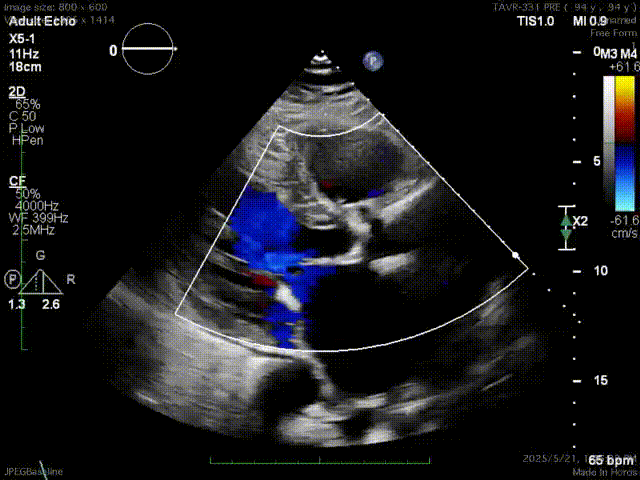

心脏超声示:

起搏器安置术后,主动脉瓣病变,退行性变可能性大,主动脉瓣狭窄(重度),左心大,左室心肌轻度肥厚,二尖瓣退行性变伴轻度反流,肺动脉压力轻度升高,三尖瓣反流(轻度)。

主动脉瓣左、右、无冠瓣弥漫性增厚,钙化,回声增强,开放受限,跨瓣血流速度加快,峰值压差约80mmHg,平均压差约44mmHg,关闭时探及微量反流。EF:56%,左室52mm。

术前心脏超声上可以看到阿婆使用了94年的瓣膜增厚、僵硬、钙化,这颗94岁的心脏平均承受着59mmHg的压力来维持叶奶奶的生命,心脏的血液以5m/s以上的速度射出狭窄的主动脉瓣口来给全身供血,主动脉瓣重度狭窄的诊断明确。